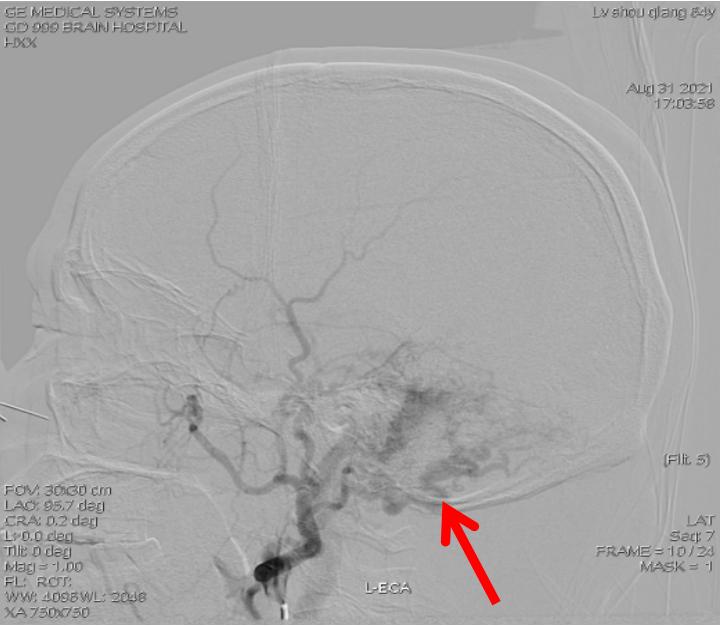

术前影像显示:左侧乙状窦区硬脑膜动静脉瘘

结合检查结果,王展航发现,卢伯的症状是由一种少见的脑血管病——硬脑膜动静脉瘘引起。这种脑血管病是由于脑部动静脉之间“短路”,会导致颅内血管杂音。“患者的耳鸣实则是颅内血管杂音。”持续性的轰鸣音是常见的临床表现,颅内血管杂音的程度与硬脑膜的血流量及部位有关。